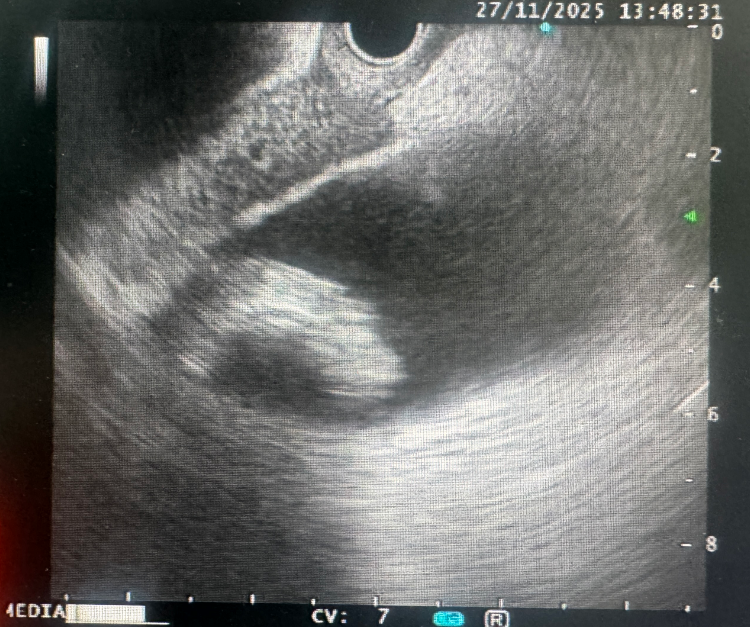

第一阶段:超声内镜下十二指肠胆囊吻合术(EUS-DCA)

手术团队在超声内镜的实时引导下,于十二指肠球部与胆囊之间建立微创引流通道,并置入支架。该操作经自然腔道进行,无需开腹,创伤小。术中成功引流脓液,患者症状迅速缓解,为后续处理巨大结石创造了条件。